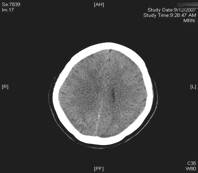

At home she developed headache again and this time headache was generalised but the pain was worse in the neck and occiput. On the tenth pos-partum day she presented to emergency department with headache and she suffered a witnessed generalised tonic-clonic seizure. No proteinuria was detected. Her blood results were essentilally normal with normal white cell count and biochemistry. A CT scan of the brain showed an area of low attenuation in the right occiput. She underwent lumbar puncture, which showed a normal opening pressure. On light microscopy no organisms were seen. The white blood cell and red blood cell counts were both <1 × 106/L. Culture showed no growth after 40 h. The CSF protein concentration was 0.3 g/L and glucose 2.9 mmol/L.

Fig. 1 Noncontrast computed tomography showing diffuse hypodensity in posterior regions bilaterally

CT can be used preliminarily to detect hypodencelesions of posterior encephalopathy, but magnetic resonance imaging (MRI) is the gold standard [1, 2, 3, 7]. Due to the widespread use of MRI this syndrome is being diagnosed more frequently. During the acute phase MRI usually reveals hyperintence on both echoes of a dual-echo T2-weighted sequences and either iso- or hypointence on T1-weighted images brain abnormalities, including both gray and white matter. Mainly involved are the parietal-occipital lobes; however, cerebellar hemispheres, basal ganglia, frontal lobes, and brainstem are also often involved [1, 13]. Fluid-attenuated inversion recovery sequences significantly improve the ability to diagnose and detect subcortical and cortical lesions in PRES over proton density and T2-weighted spin-echo images and therefore should be performed in patients with suspected PRES to allow more confident recognition of the often subtle imaging abnormalities[13]. Diffusion weighted MRI has been demonstrated to be particularly sensitive to changes in distribution of water in the brain and can detect white matter edema early and reliably differentiate between vasogenic and cytotoxic edema in these patients (Fig. 1) [7, 8].